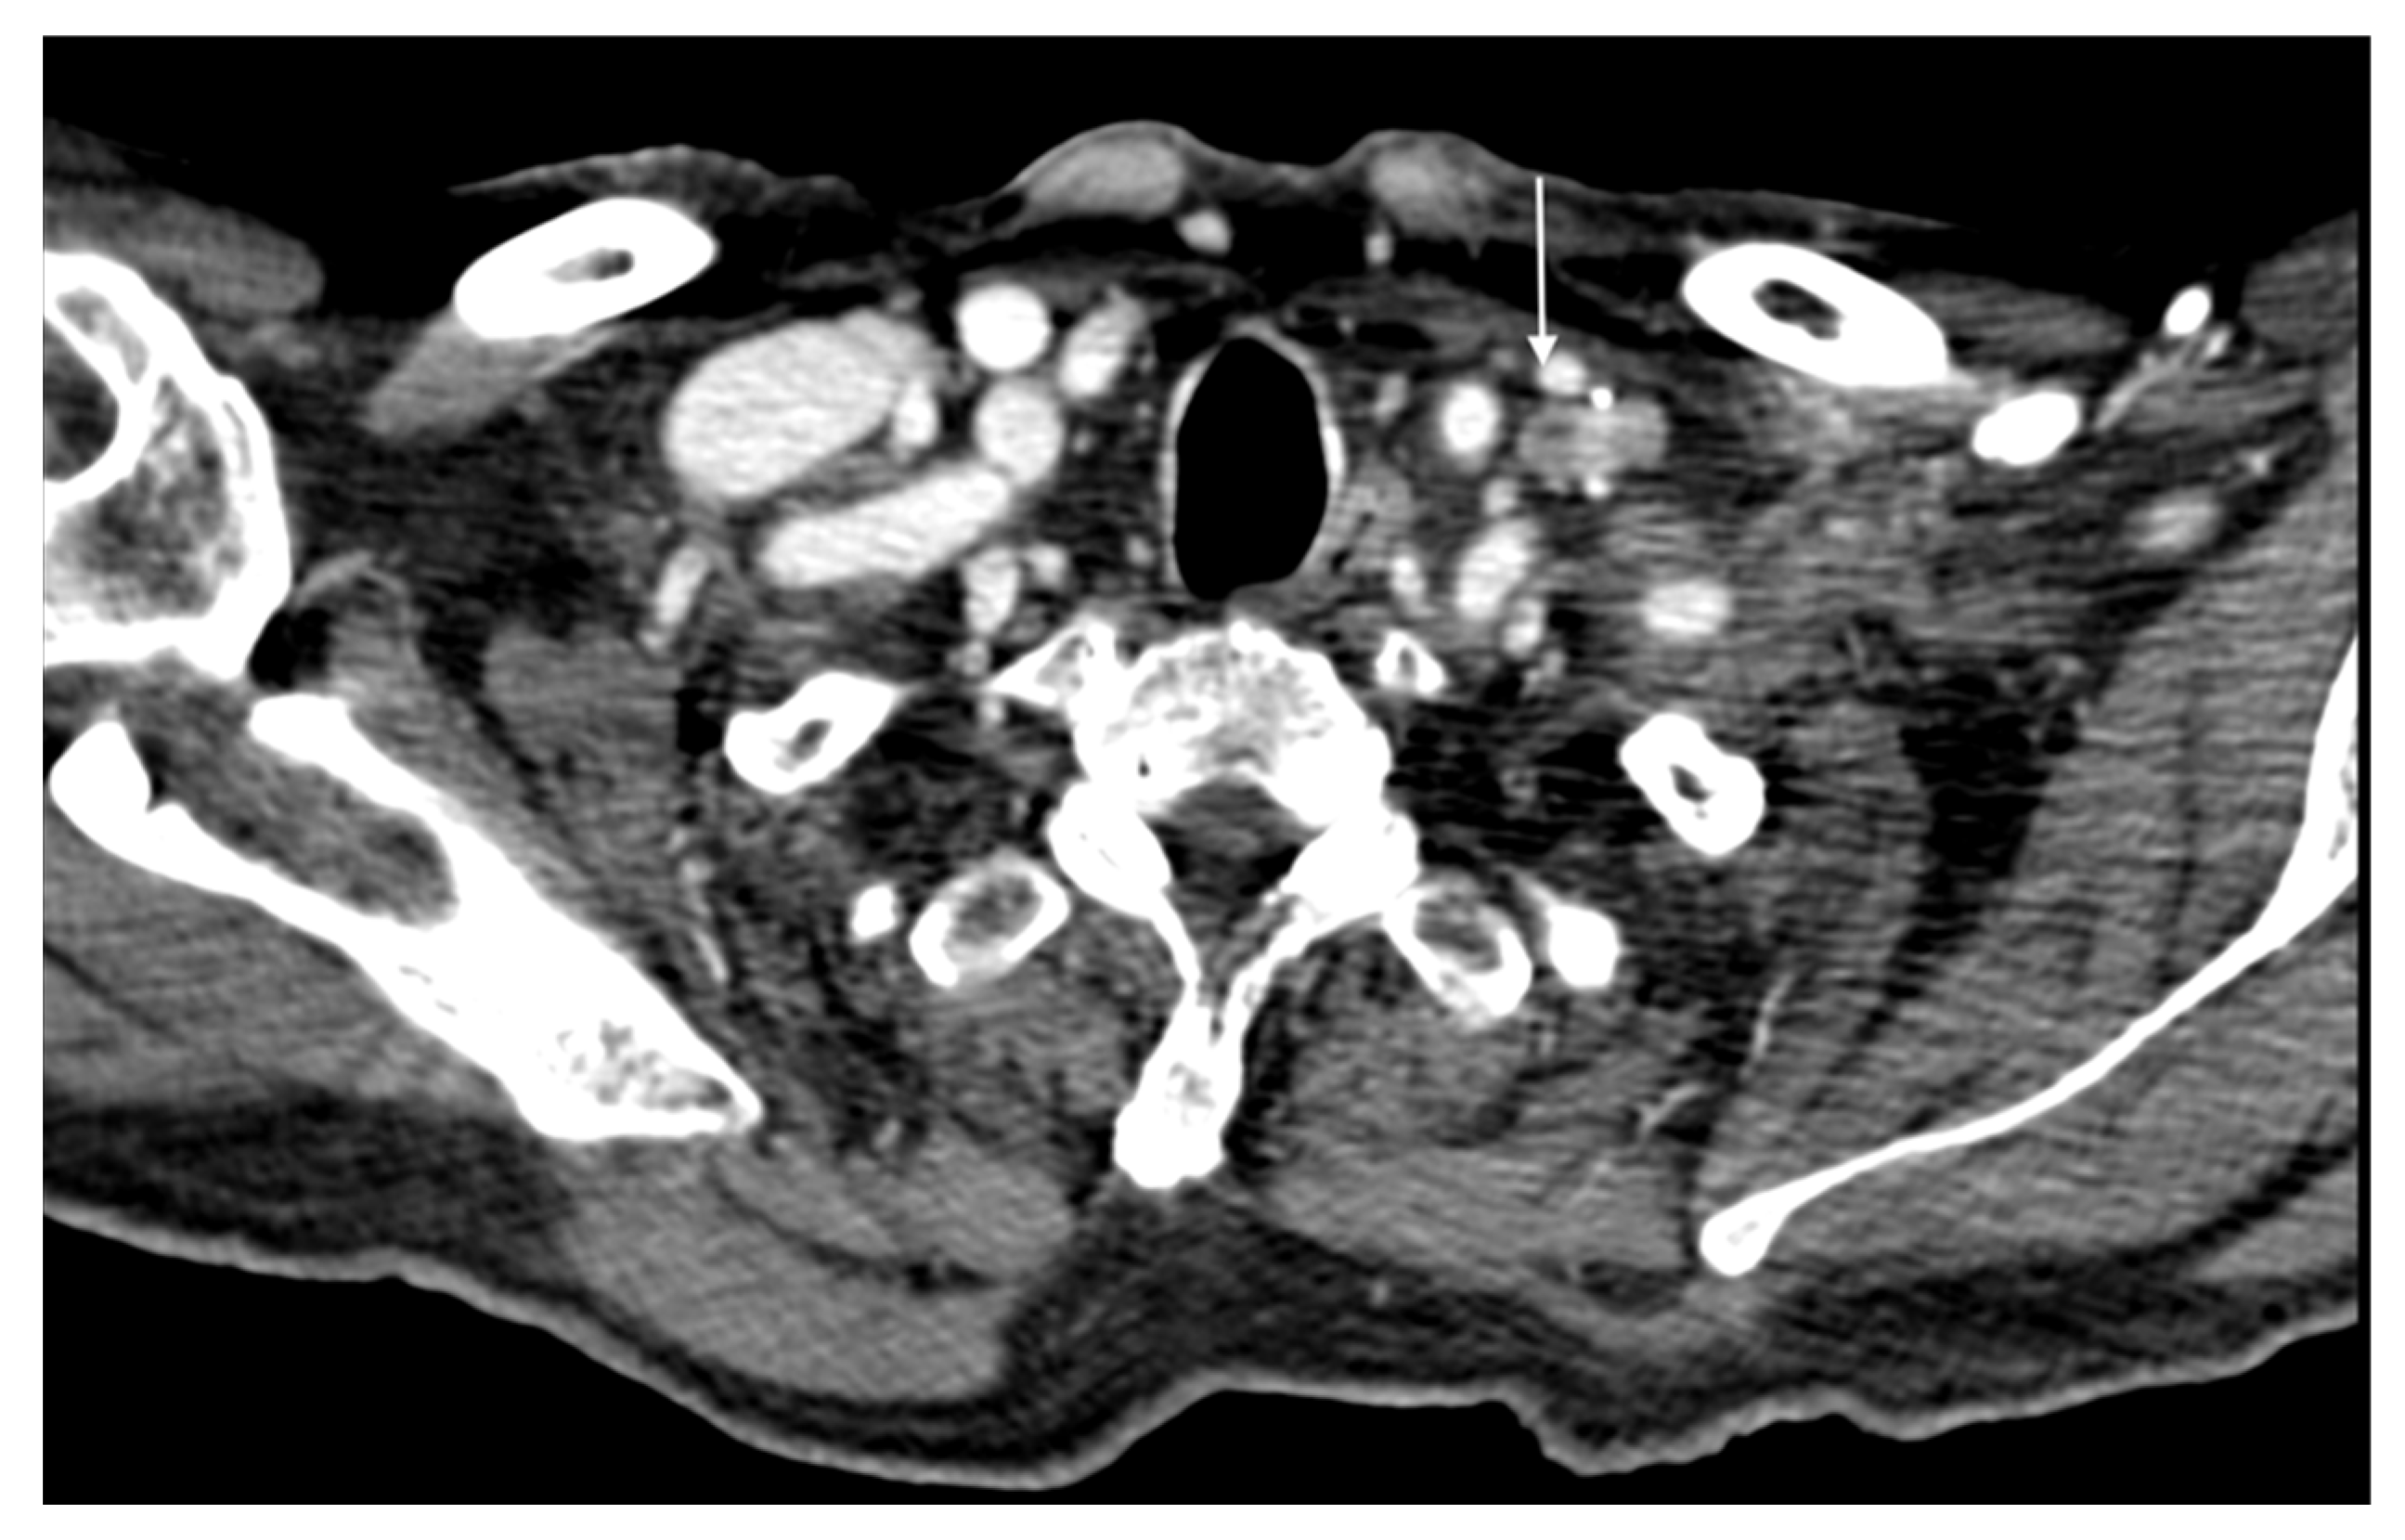

7. The Role of Imaging in Cutaneous Squamous Cell Carcinoma

7.1. CTA Protocol

8. Follow-Up Imaging

- Fox, M.; Brown, M.; Golda, N.; Goldberg, D.; Miller, C.; Pugliano-Mauro, M.; Schmults, C.; Shin, T.; Stasko, T.; Xu, Y.G.; et al. Nodal Staging of High-Risk Cutaneous Squamous Cell Carcinoma. J. Am. Acad. Dermatol. 2019, 81, 548–557. [Google Scholar] [CrossRef]

- Tokez, S.; Koekelkoren, F.H.J.; Baatenburg De Jong, R.J.; Grünhagen, D.J.; Mooyaart, A.L.; Nijsten, T.; Van Der Lugt, A.; Wakkee, M. Assessment of the Diagnostic Accuracy of Baseline Clinical Examination and Ultrasonographic Imaging for the Detection of Lymph Node Metastasis in Patients with High-Risk Cutaneous Squamous Cell Carcinoma of the Head and Neck. JAMA Dermatol. 2022, 158, 151–159. [Google Scholar] [CrossRef] [PubMed]

- Eggermont, C.; Nené, L.E.H.; Koekelkoren, F.H.J.; van der Toorn, Y.R.; Snetselaar, L.D.; Kroah-Hartman, M.; Genders, R.E.; Kelleners-Smeets, N.W.J.; Hollestein, L.M.; van Kester, M.S.; et al. The impact of routine ultrasonography on nodal metastasis in head and neck cutaneous squamous cell carcinoma: A retrospective multicentre cohort study. J. Eur. Acad. Dermatol. Venereol. 2023, 37, e1136–e1140. [Google Scholar] [CrossRef] [PubMed]

- Humphreys, T.R.; Shah, K.; Wysong, A.; Lexa, F.; MacFarlane, D. The role of imaging in the management of patients with nonmelanoma skin cancer: When is imaging necessary? J. Am. Acad. Dermatol. 2017, 76, 591–607, Erratum in J. Am. Acad. Dermatol. 2017, 76, 1226. [Google Scholar] [CrossRef] [PubMed]

- MacFarlane, D.; Shah, K.; Wysong, A.; Wortsman, X.; Humphreys, T.R. The role of imaging in the management of patients with nonmelanoma skin cancer: Diagnostic modalities and applications. J. Am. Acad. Dermatol. 2017, 76, 579–588. [Google Scholar] [CrossRef] [PubMed]